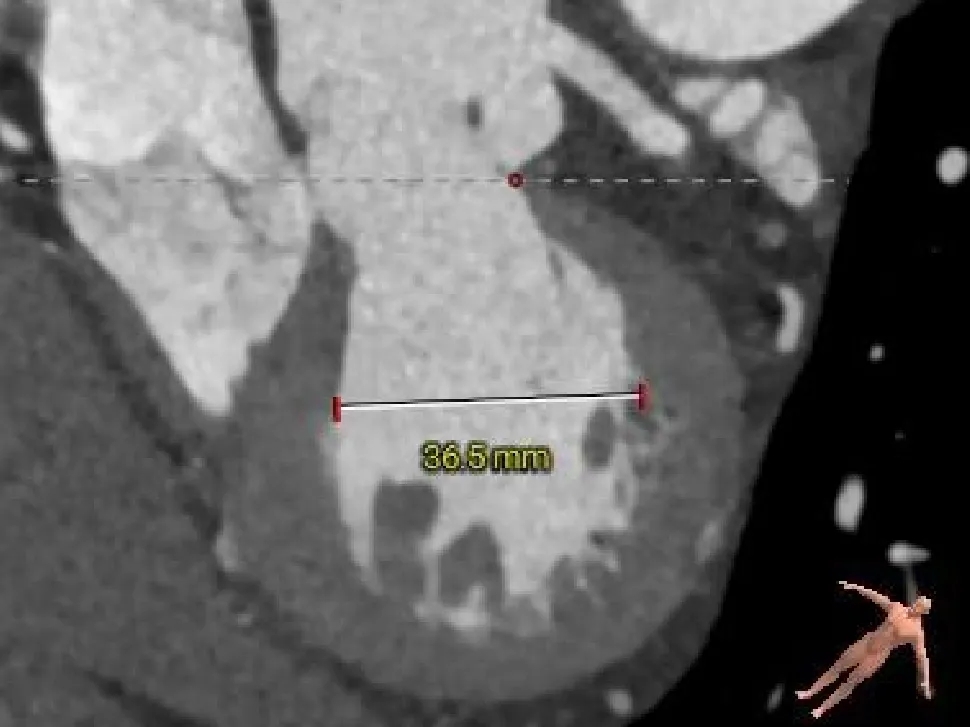

主动脉根部测量

Annulus

23.6mm

LVOT

21.9mm

VR图

SOV:

35.2*32.7*31.9mm

STJ:

33.3mm

AAO:

44.6mm